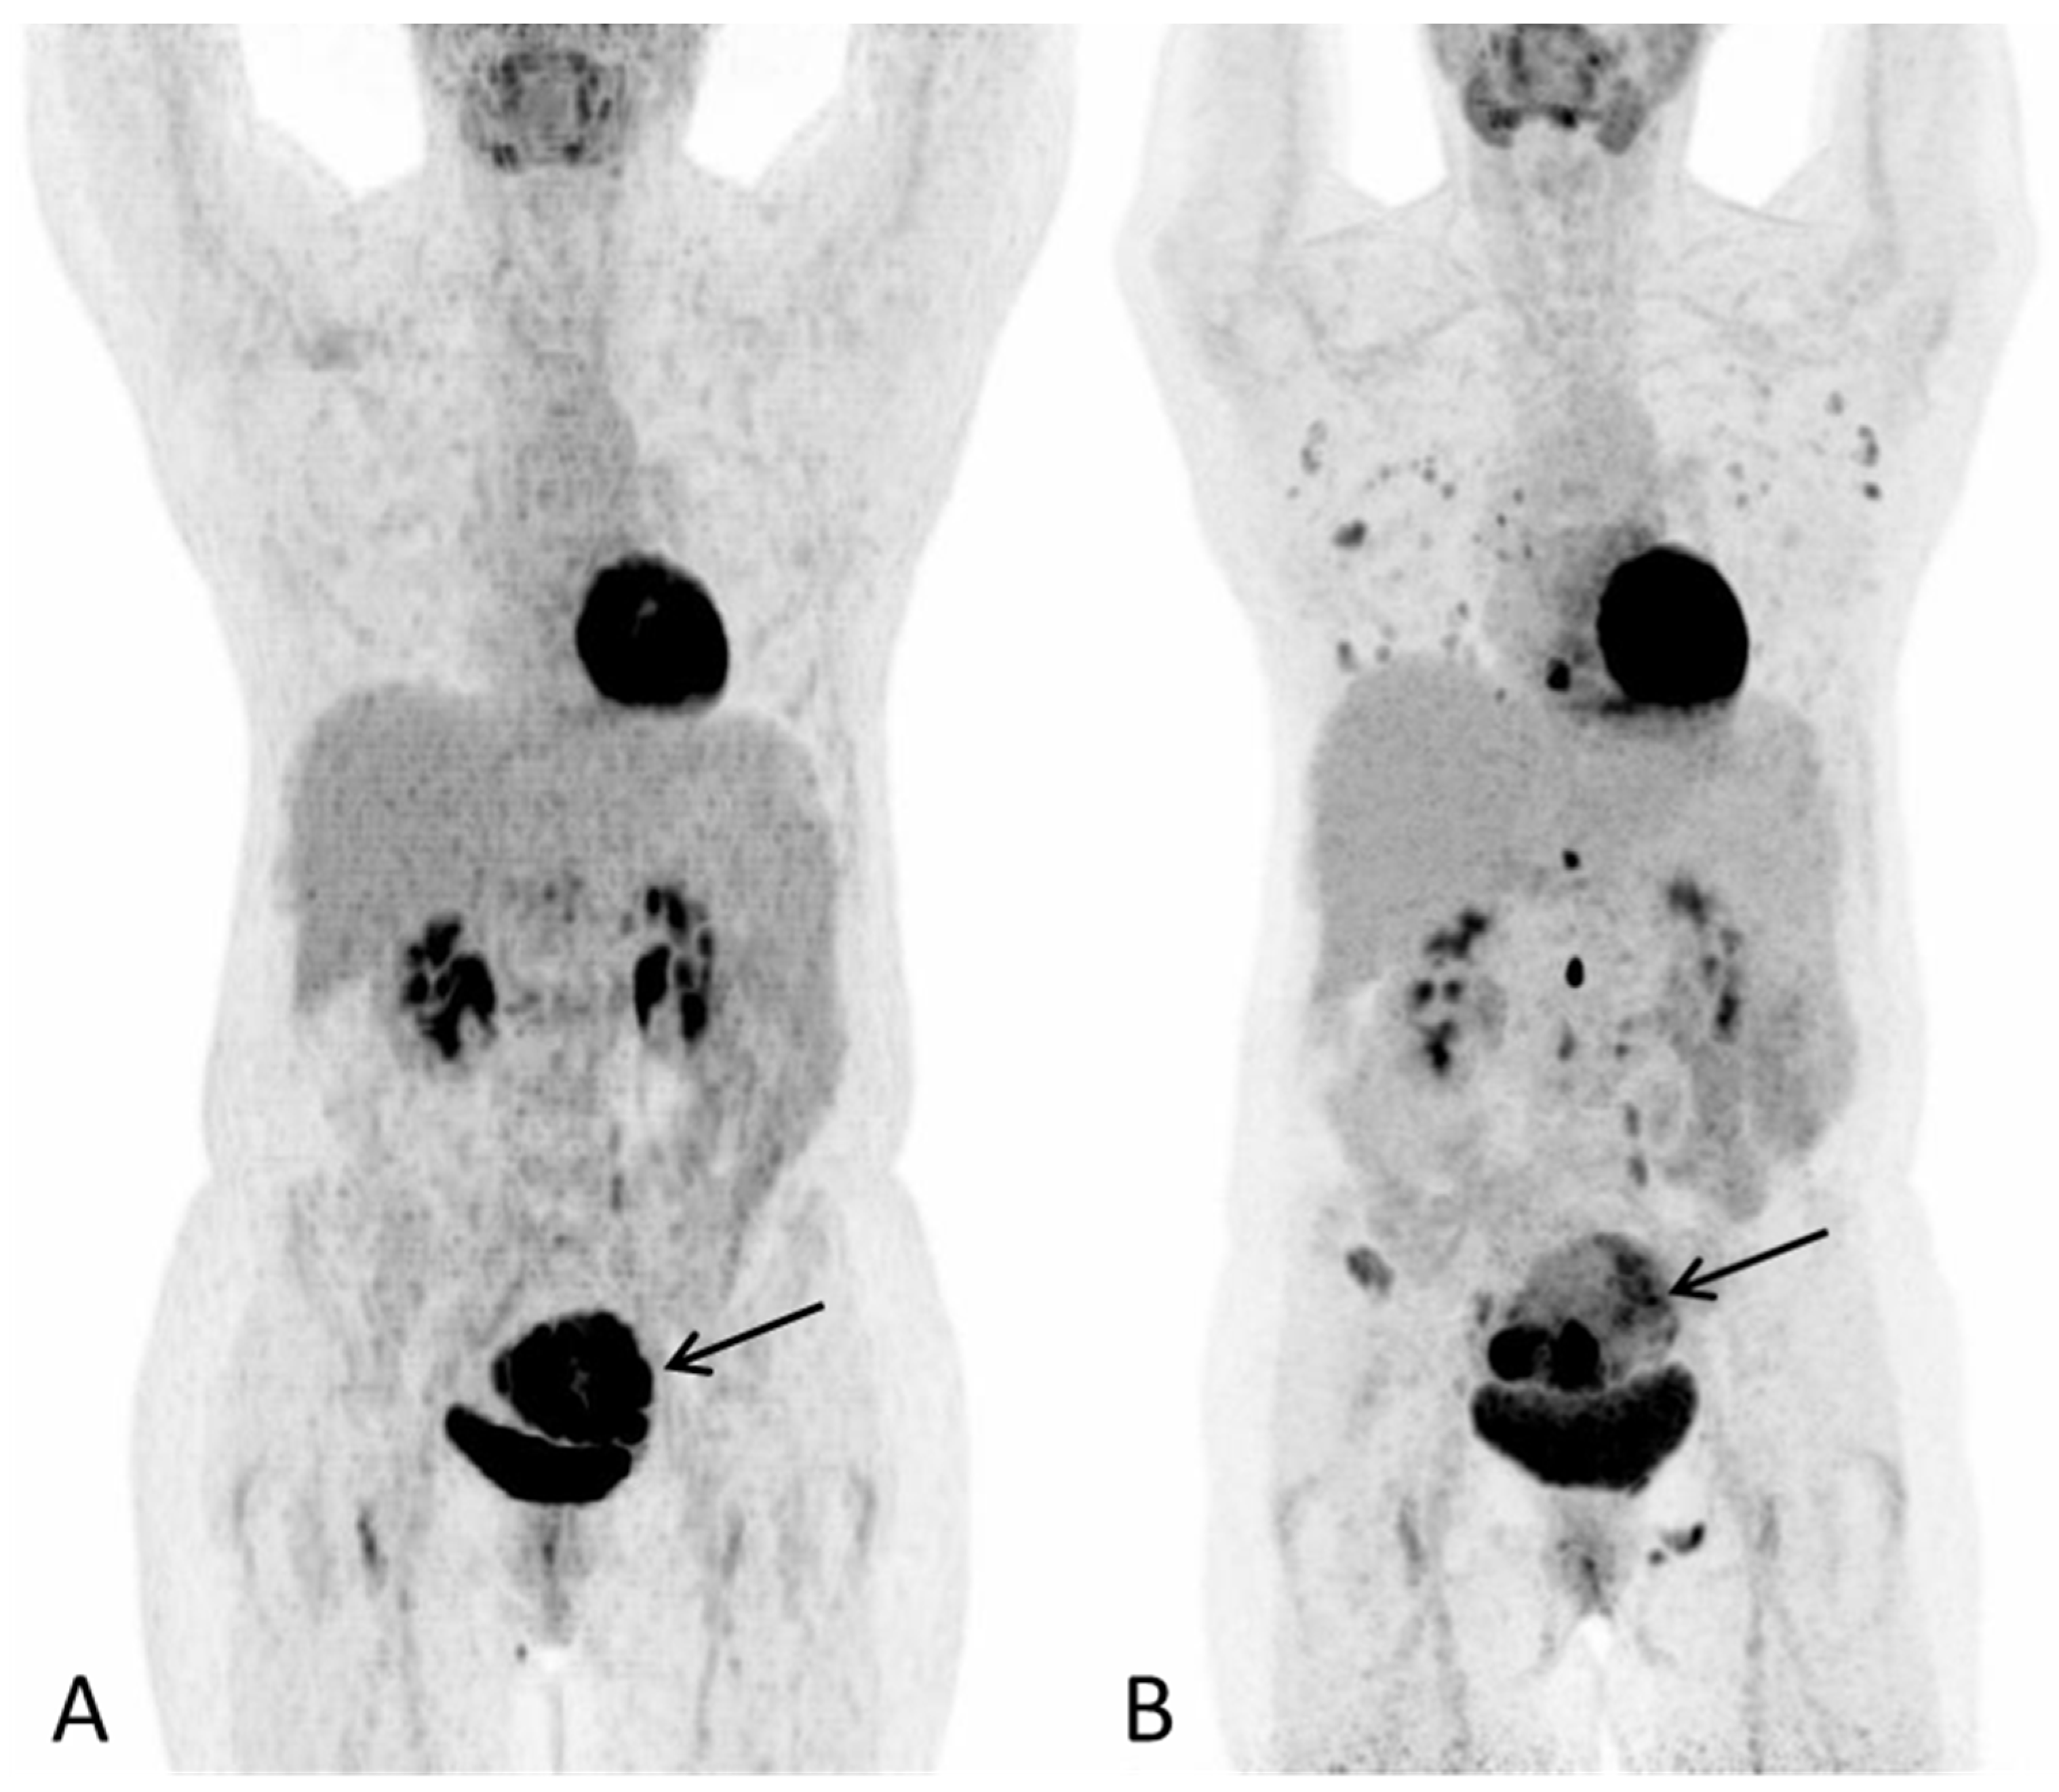

Disseminated Primary Uterine Hepatoid Adenocarcinoma with α-Fetoprotein Production Demonstrated on 18F-FDG PET/CT

Dejanovic, D.; Boennelycke, M.; Amtoft, A.G.; Christensen, C.B.; Wetterstroem, V.; Loft, A.; Noettrup, T.J. Disseminated Primary Uterine Hepatoid Adenocarcinoma with α-Fetoprotein Production Demonstrated on 18F-FDG PET/CT. Diagnostics 2022, 12, 1447. https://doi.org/10.3390/diagnostics12061447